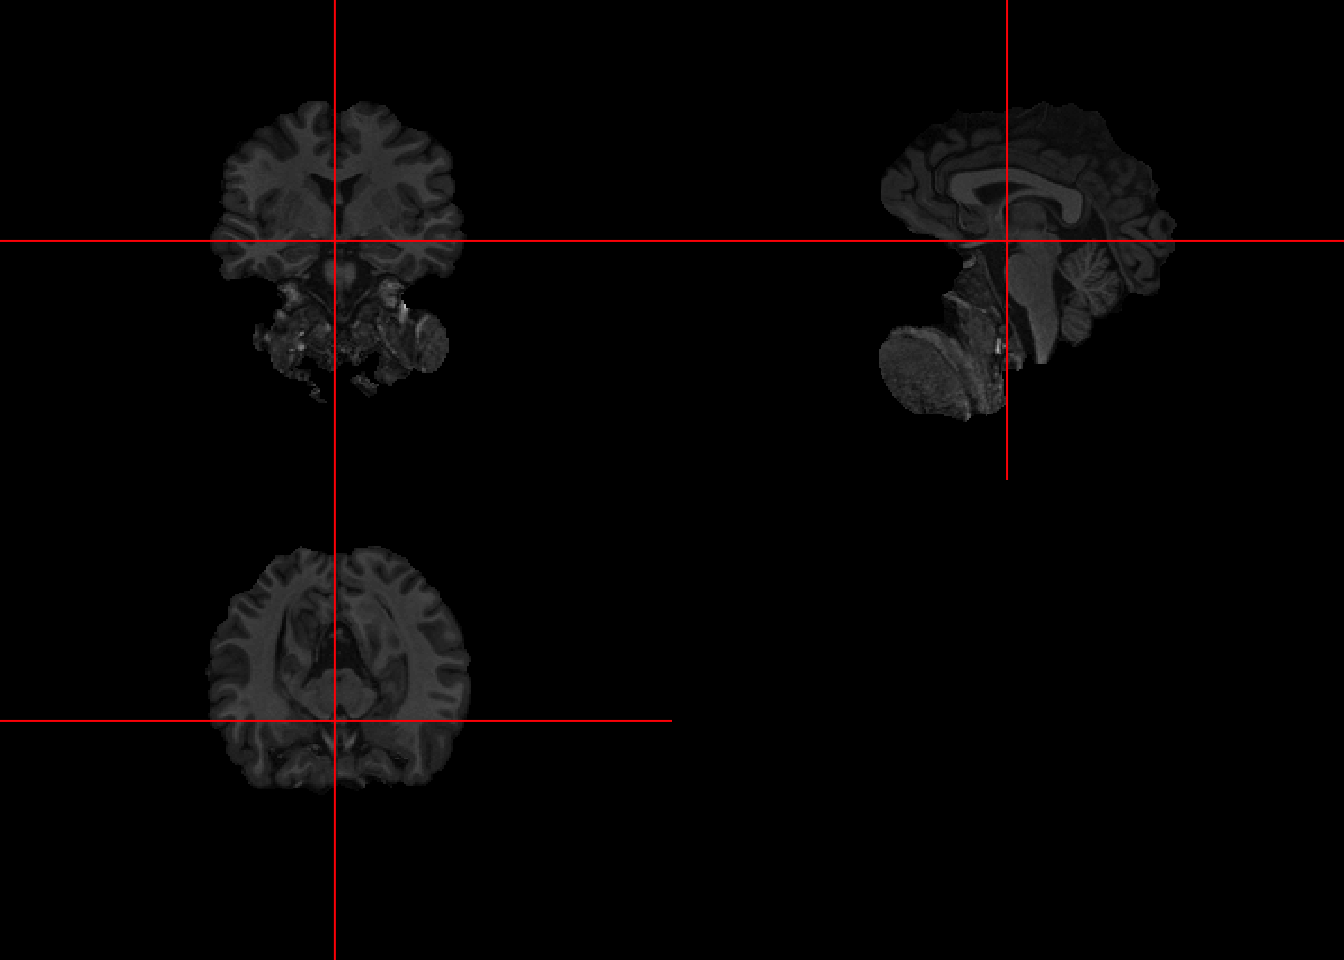

7.4 Improving Brain Extraction

To improve upon the results, a second pass can be done taking into account the center of gravity.

bet_fast2 = fslbet(infile = fast_img, retimg = TRUE, opts = cog)## FSLDIR='/usr/local/fsl'; PATH=${FSLDIR}/bin:${PATH};export PATH FSLDIR; sh "${FSLDIR}/etc/fslconf/fsl.sh"; FSLOUTPUTTYPE=NIFTI_GZ; export FSLOUTPUTTYPE; ${FSLDIR}/bin/bet2 "/private/var/folders/wk/jzm8xd01507b9nx7qmycj7700000gn/T/RtmpmusoTp/file2c314582822.nii.gz" "/var/folders/wk/jzm8xd01507b9nx7qmycj7700000gn/T//RtmpmusoTp/file2c313a31728f" -c 88 140 129

7.5 Visualizing first and second pass

The results have improved, removing much of the lower non-brain sections. However, we can see the results are not perfect so it’s important to visually inspect each image at each phase of the processing pipeline.